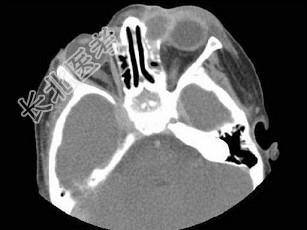

- 多项选择题女,2岁, 左侧眼睑肿胀发热,CT检查如图所示, 正确的描述或诊断是 ( )

A、左侧鼻骨外侧旁见软组织块影

B、其内密度不均,可见低密度影

C、左侧鼻泪管囊肿

D、鼻泪管脓肿

E、混合瘤